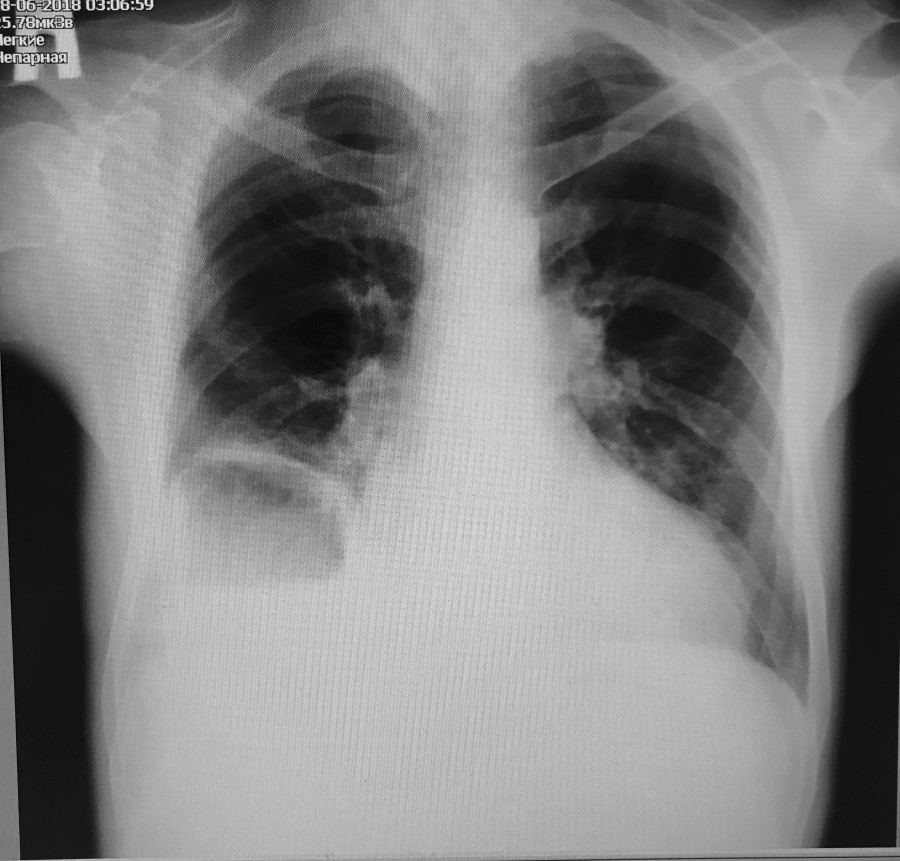

полисегментарная деструктивная пневмония с абсцессом легкого

42807782_3_1342518.jpg

42807782_3_1342518.jpg [ 41.97 KiB | Просмотров: 15107 ]